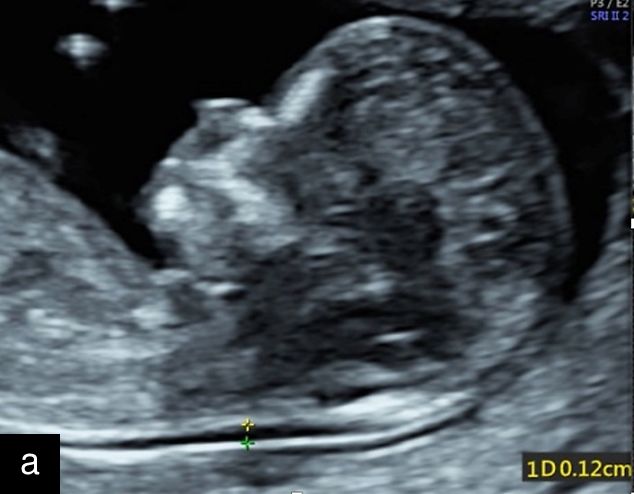

5

Sagittal ultrasound images, showing normal nuchal translucency (NT) at 12 weeks (a) and increased NT at 13 weeks (b).